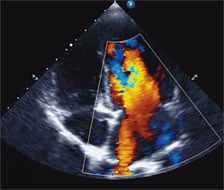

Photo of Pulmonary HypertensionPulmonary hypertension (PH) can present at any age from infancy to adulthood. In the pediatric population, it can be inherited, associated with other conditions such as congenital heart disease or chronic lung disease, or occur with no clear etiology (idiopathic pulmonary arterial hypertension, or IPAH). It is difficult to identify the true incidence of this disease in children, but some registry data suggests a yearly rate of 64 cases per 1 million children.1

An echocardiogram showed evidence of severe right ventricular hypertension due to elevated pulmonary pressure, which was confirmed via catheterization. We diagnosed her with IPAH and immediately started her on pulmonary vasodilators in an effort to reduce the pulmonary pressures.

Correcting the lesion would require several interventional radiology procedures to occlude the AVM. However, tolerating these procedures was going to be difficult in the setting of severe PH. Therefore, after confirming his PH by echocardiography and cardiac catheterization, he was quickly escalated on PH-specific medications. This included a continuous subcutaneous infusion of a prostacyclin (treprostinil) to reduce the PH and improve cardiovascular function. It is routinely used in adults with severe pulmonary hypertension, but at this time treprostinil was rarely used in young infants.4 However, given our familiarity with this drug and our experience with infant PH, we felt comfortable using it for HT, who tolerated it very well.